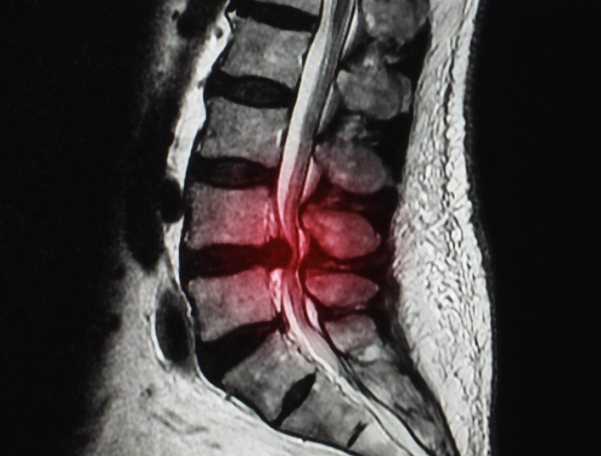

Sciatica is a common condition characterised by pain that radiates along the path of the sciatic nerve, which branches from your lower back through your hips and buttocks and down each leg. It typically affects only one side of the body. The underlying cause of sciatica is usually pressure on or irritation of the sciatic nerve, most often as a result of a herniated disc, bone spur on the spine, or narrowing of the spine (spinal stenosis). This pressure can lead to inflammation, pain, and sometimes numbness in the affected leg.

What Causes Sciatica

Sciatica can be caused by a variety of spinal conditions that impinge on the sciatic nerve roots. Some common causes include:

- Herniated or protruding disc: The soft, gel-like centre of a spinal disc bulges out and presses on the nerve roots.